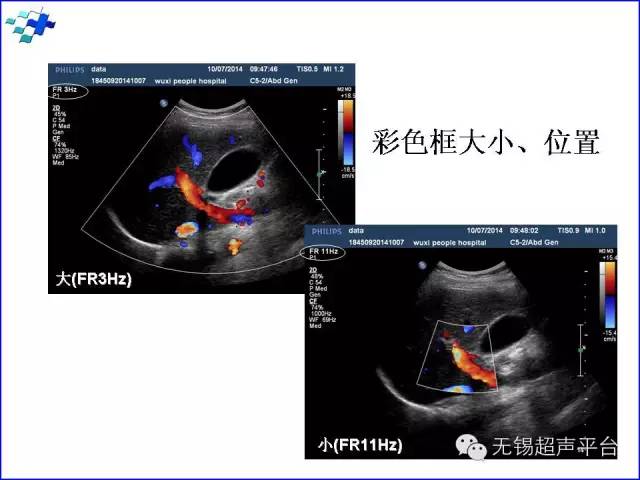

线密度(line density):线密度增加时,帧频降低,但彩色多普勒所包含的信息增加,心血池、心室壁与室间隔之间的分界更清晰。设置时需要平衡线密度和频率之间的关系,尽可能在可接收的帧频下达到较高的线密度。